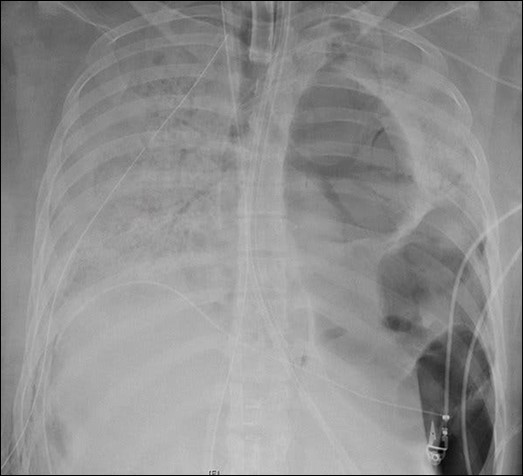

A 20-years-female received a double lung transplant following end-stage lung disease (Figure 1 & Figure 2) by COVID-19 at Northwestern Medicine in Chicago12. She was the first COVID-19 lung transplant case for the United States of America12. COVID-19 pandemic which started from China outspread to Europe and the United States of America, reached to South Asian countries at last. Thus this provides us with an opportunity to act accordingly those already affected countries have acted to control this pandemic before it is out of control. In Nepal there are many cardiothoracic and vascular surgeons capable enough for lung transplantation, however its legal system lag behind the clinical system. The first law enacted to regulate human organ transplantation in Nepal with title "The Human Body Organ Transplantation (Regulation and Prohibition) Act, 2055 (1998) provides provision for only Kidney transplantation as solid organ transplantation13. Recent modification in the existing law in the form of Human Body Organ Transplantation (Regulation and Prohibition) Act 207214 and Human Body Organ Transplantation (Regulation and Prohibition) legislation 207315 has provided provision for Liver transplantation too but not for other solid organ transplantation like lung. Keeping in view of urgent need of lung transplantation to save the life of end-stage COVID-19 cases as shown in the cases done in China, Europe and the United States of America, this research has been done as a small step towards the preparedness for ongoing COVID-19 pandemic with an aim to see the perception of health care professionals of tertiary care centre of eastern Nepal regarding the legal aspects of lung transplantation.

Figure 1.An X-ray of the patient’s lungs before surgery. Northwestern Medicine